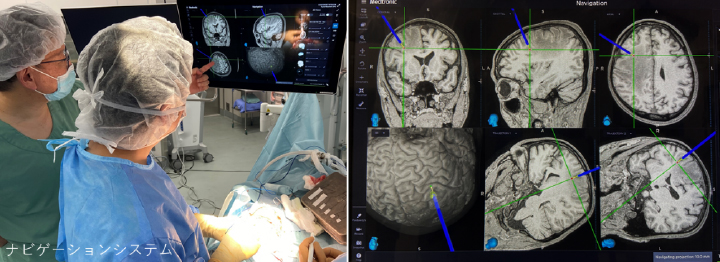

3.ナビゲーションシステム:

必要に応じて術前に準備し、MRIやCT画像の中でどこを操作しているのかを確認しながら手術を行います。手術野に見えていない部分でもナビゲーションの画面上で確認することができるため、手術操作に注意を要する部があらかじめ確認でき、病変の取り残しなどを防ぐことができます。

造影MRIで、悪性脳腫瘍(神経膠芽腫)を認めました(黄矢印)。顕微鏡、術中モニタリング、ナビゲーション、術中超音波検査を駆使して腫瘍を摘出し、術後放射線治療を行いました。

その他、脳腫瘍、脊椎脊髄疾患、顔面けいれんなどにつきましては、術中モニタリングやナビゲーション、ハイブリッド手術室等を使用して、安全性を担保しながら手術を行っています。